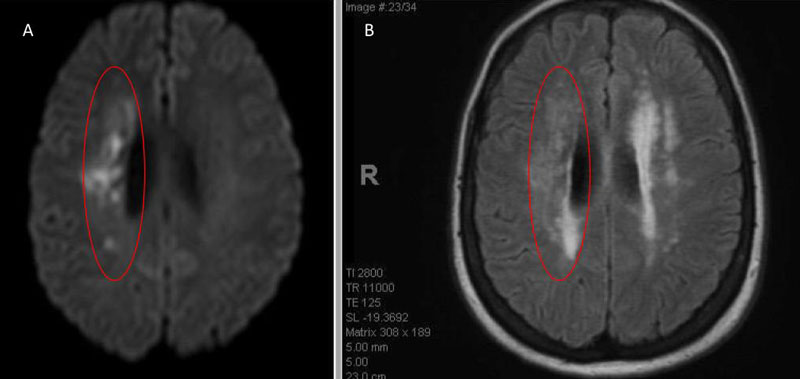

An MRI confirmed diffusion and FLAIR positive ischemic strokes within the deep periventricular white matter compatible with a “watershed” distribution of injury (Figure 3).

Figure 3. A) MRI Diffusion and B) FLAIR sequence confirm ischemic damage in the right periventricular deep white matter “Watershed” territories.

Severe Carotid Stenosis has multiple pathophysiologic mechanisms that may resulting in mild to severe symptomatic presentations. Often, carotid-embolic events precipitate Large Vessel Occlusions of the MCA or ICA (less frequently ACA) with associated spectrum of malignant stroke syndromes based on the location, timing, comorbidities, and collateral perfusion of the patients. In our patient, the pattern of symptoms she experienced were mild and repetitive, with her deficits recovering and recurring, ultimately prompting medical attention. Her Brain Perfusion Imaging and MRI Ischemic pattern suggested a strong hemodynamic component to her ischemic injury, classically described as a “Watershed” pattern (WS). WS has often been further differentiated into Internal WS which effects the distal fields of 2 non-anastomosing arterial systems (i.e. ACA-MCA-PCA), resulting in 2 distinct WS areas: 1) in the cortical territories or Cortical Watershed (CWS); and 2) in the white matter along and above the lateral ventricle of the Centrum Semiovale – “string of pearls” termed the Internal Watershed (IWS). IWS ischemia favors a hemodynamic mechanism while purely CWS may be secondary to microembolic occlusions. A combination of IWS and CWS may indicate both hemodynamic perfusion deficits and microemboli.1 Our patient’s pattern of deep white matter involvement, angiographic anatomy, collaterals, and perfusion profile strongly favored IWS ischemia secondary to a hemodynamic perfusion failure.